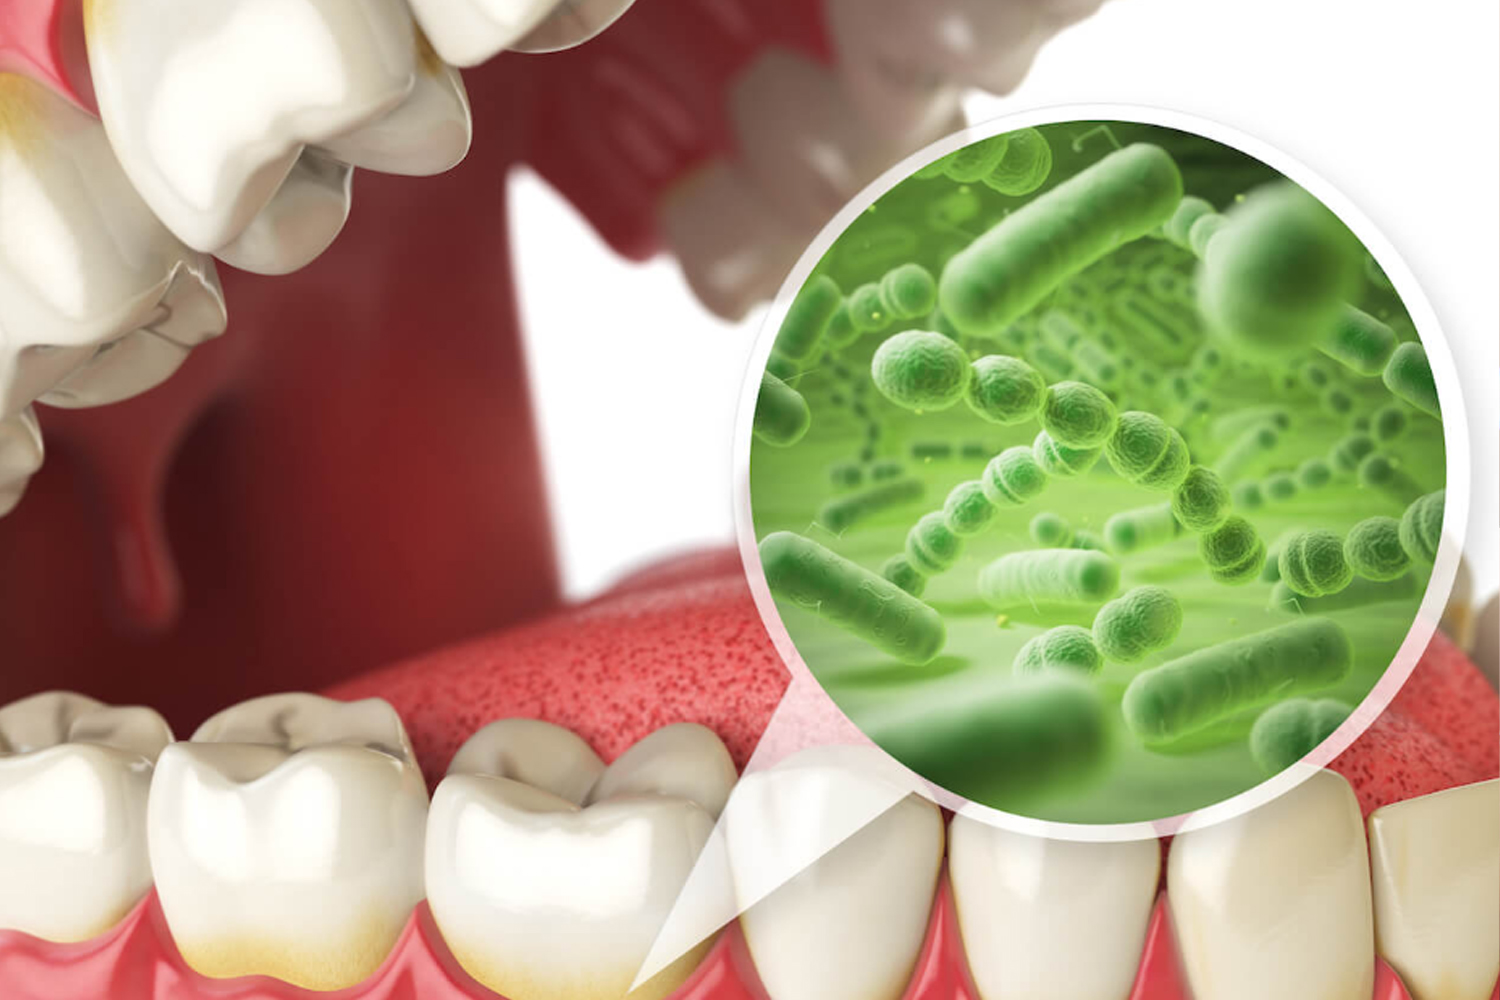

歯周病の原因と進行

お口の中には、常に数百種類の細菌が存在しています。その一部が歯のまわりに “ねばつく汚れの膜(プラーク)”をつくり、歯ぐきに炎症を起こします。これが歯周病のはじまりです。進行すると歯を支える骨が少しずつ失われていきます。